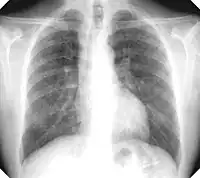

There are three key elements to the diagnosis of silicosis. First, the patient history should reveal exposure to sufficient silica dust to cause this illness. Second, chest imaging (usually chest x-ray) that reveals findings consistent with silicosis. Third, there are no underlying illnesses that are more likely to be causing the abnormalities. Physical examination is usually unremarkable unless there is complicated disease. The examination findings are not specific for silicosis.[19]

For uncomplicated silicosis, chest x-ray will confirm the presence of small (< 10 mm) nodules in the lungs, especially in the upper lung zones. Using the ILO classification system, these are of profusion 1/0 or greater and shape/size "p", "q", or "r". Lung zone involvement and profusion increases with disease progression. In advanced cases of silicosis, large opacity (> 1 cm) occurs from coalescence of small opacities, particularly in the upper lung zones.

With retraction of the lung tissue, there is compensatory emphysema. Enlargement of the hilum is common with chronic and accelerated silicosis. In about 5–10% of cases, the nodes will calcify circumferentially, producing so-called "eggshell" calcification. This finding is not pathognomonic (diagnostic) of silicosis. In some cases, the pulmonary nodules may also become calcified.

Chest X-ray showing uncomplicated silicosis